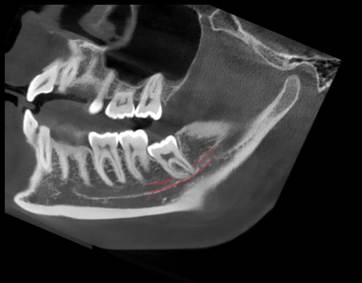

Спустя примерно четыре недели делается повторный КТ-снимок или другой рентген. Врач делает небольшой надрез, удаляет мини-винт, а затем — сам зуб.

До и после экструзии:

И ещё одно до и после: